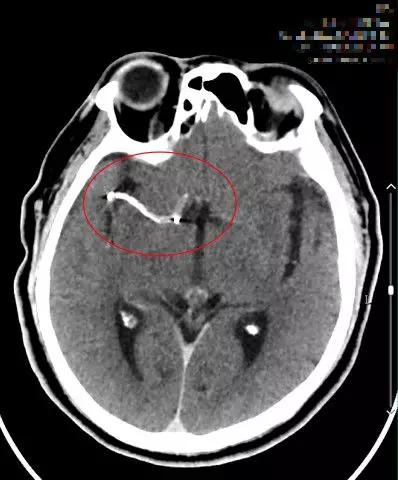

入院时头颅CT(07:48分)

复查头颅CT(09:48分)

术后即刻复查头颅CT(17:33分)